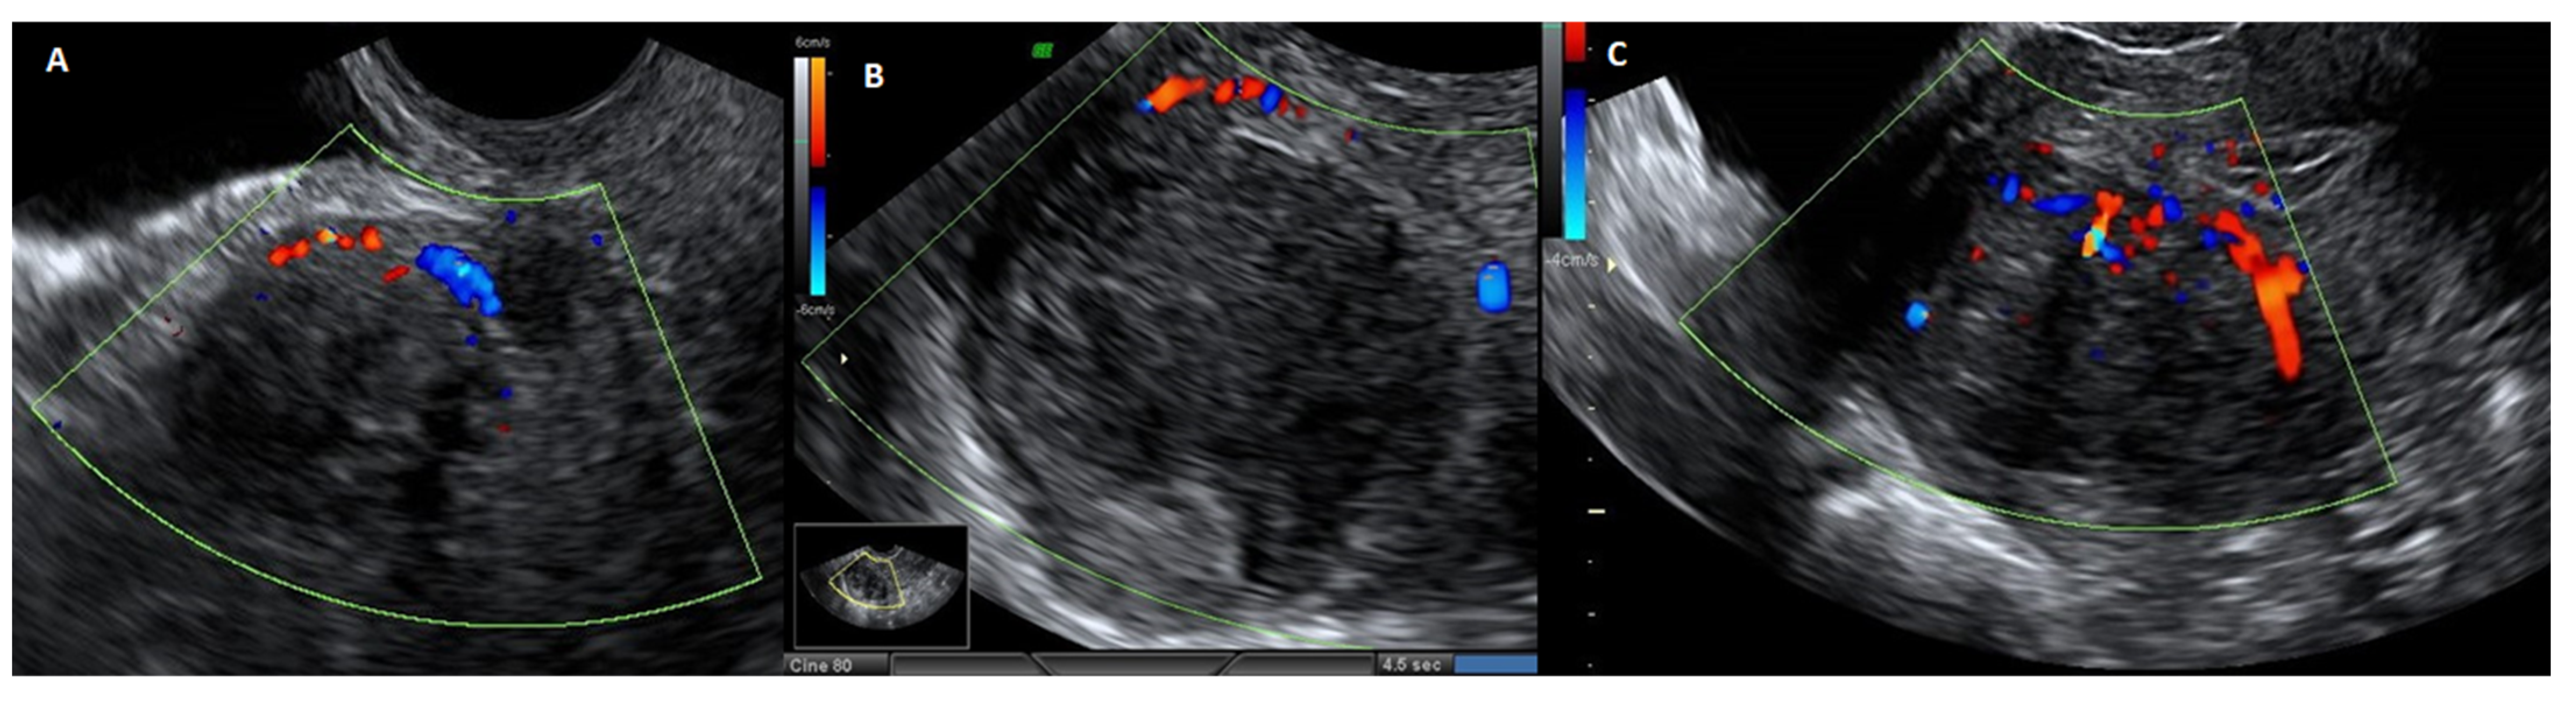

Figure 5.

Ultrasound image with echodoppler of fibroma with overlying pseudocapsule: (A) on the left, vascular ring of fire of the pseudocapsule, which is included in the vascular ring; (B) in the center, fibroma without internal vascularization; (C) on the right, the vascular ring of fire of the pseudocapsule, with vessels detaching from the pseudocapsule and penetrating from the periphery of myoma towards the center of the fibroma.

Transabdominal and transvaginal sonography reveals the pseudocapsule as an echogenic line encircling the myoma, with a wall that is at least one centimeter distinct and augmented by distal echoes. In ultrasound Doppler imaging, the myoma pseudocapsule manifests as a “ring of fire”, whereas histological images reveal a clear demarcation separating it from the myometrium. Although the myoma pseudocapsule’s vasculature may have structural flaws that make it brittle, the pseudocapsule is composed of the same cell types and exhibits the same biological structure as the nearby myometrium [].